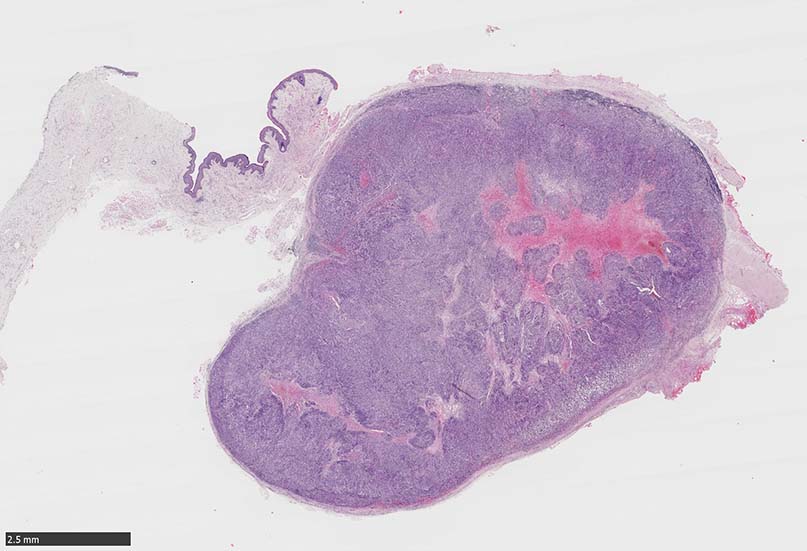

SPS244-Case01 右下眼瞼腫瘤 70歳代女性

SPS244-Case02 項部皮下腫瘤 70歳代女性

潰瘍びらんはない割面loupe像